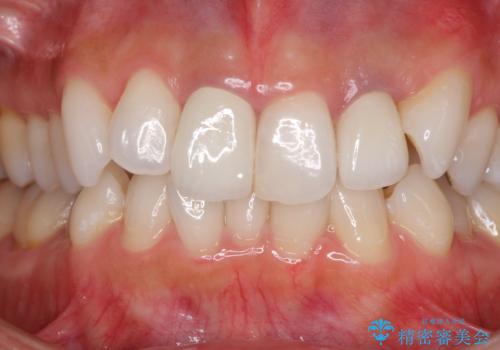

2歯をオールセラミッククラウン(ジルコニアクラウン)にて補綴することとしました。

土台の金属はグラスファイバーを含有したものに、クラウンの土台は強化セラミックとすることで、自然な前歯に仕上がりました。